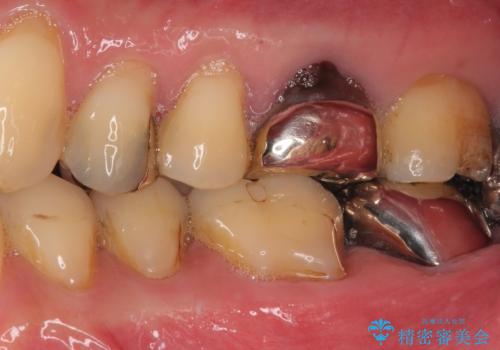

- 奥歯で食事がとれないくらいに痛むとのことで来院された患者です。

診察の結果、既に根管治療をされている第二大臼歯の根尖部に大きな病変があり、それが痛みの原因であるため、根管治療が必要と判断されました。

速やかに根管治療を行い、痛みの消退を確認の後、オールセラミッククラウンにて補綴治療を行うこととしました。